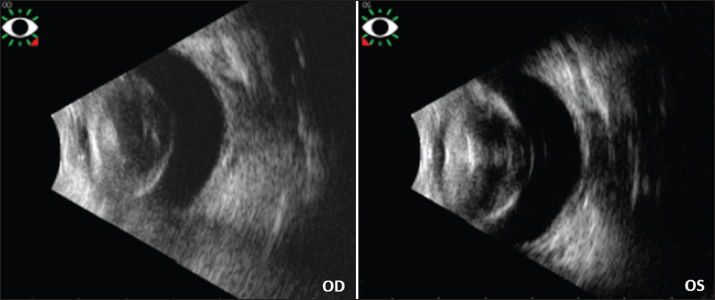

Ocular ultrasonography

Vitreoretinal ultrasonography (Vu Max HD, Sonomed Escalon, Lake Success, NY, USA) was performed OU by use of a 20-MHz ultrasound probe revealing bilateral hypermature cataracts, without retinal detachment neither vitreous anomaly nor lens displacement (Fig. 4).

Fig. 4. Ultrasound images of the rabbit’s both eyes. Note for each eye the thickened and opaque lens, without lens displacement nor retinal detachment nor vitreous anomaly.